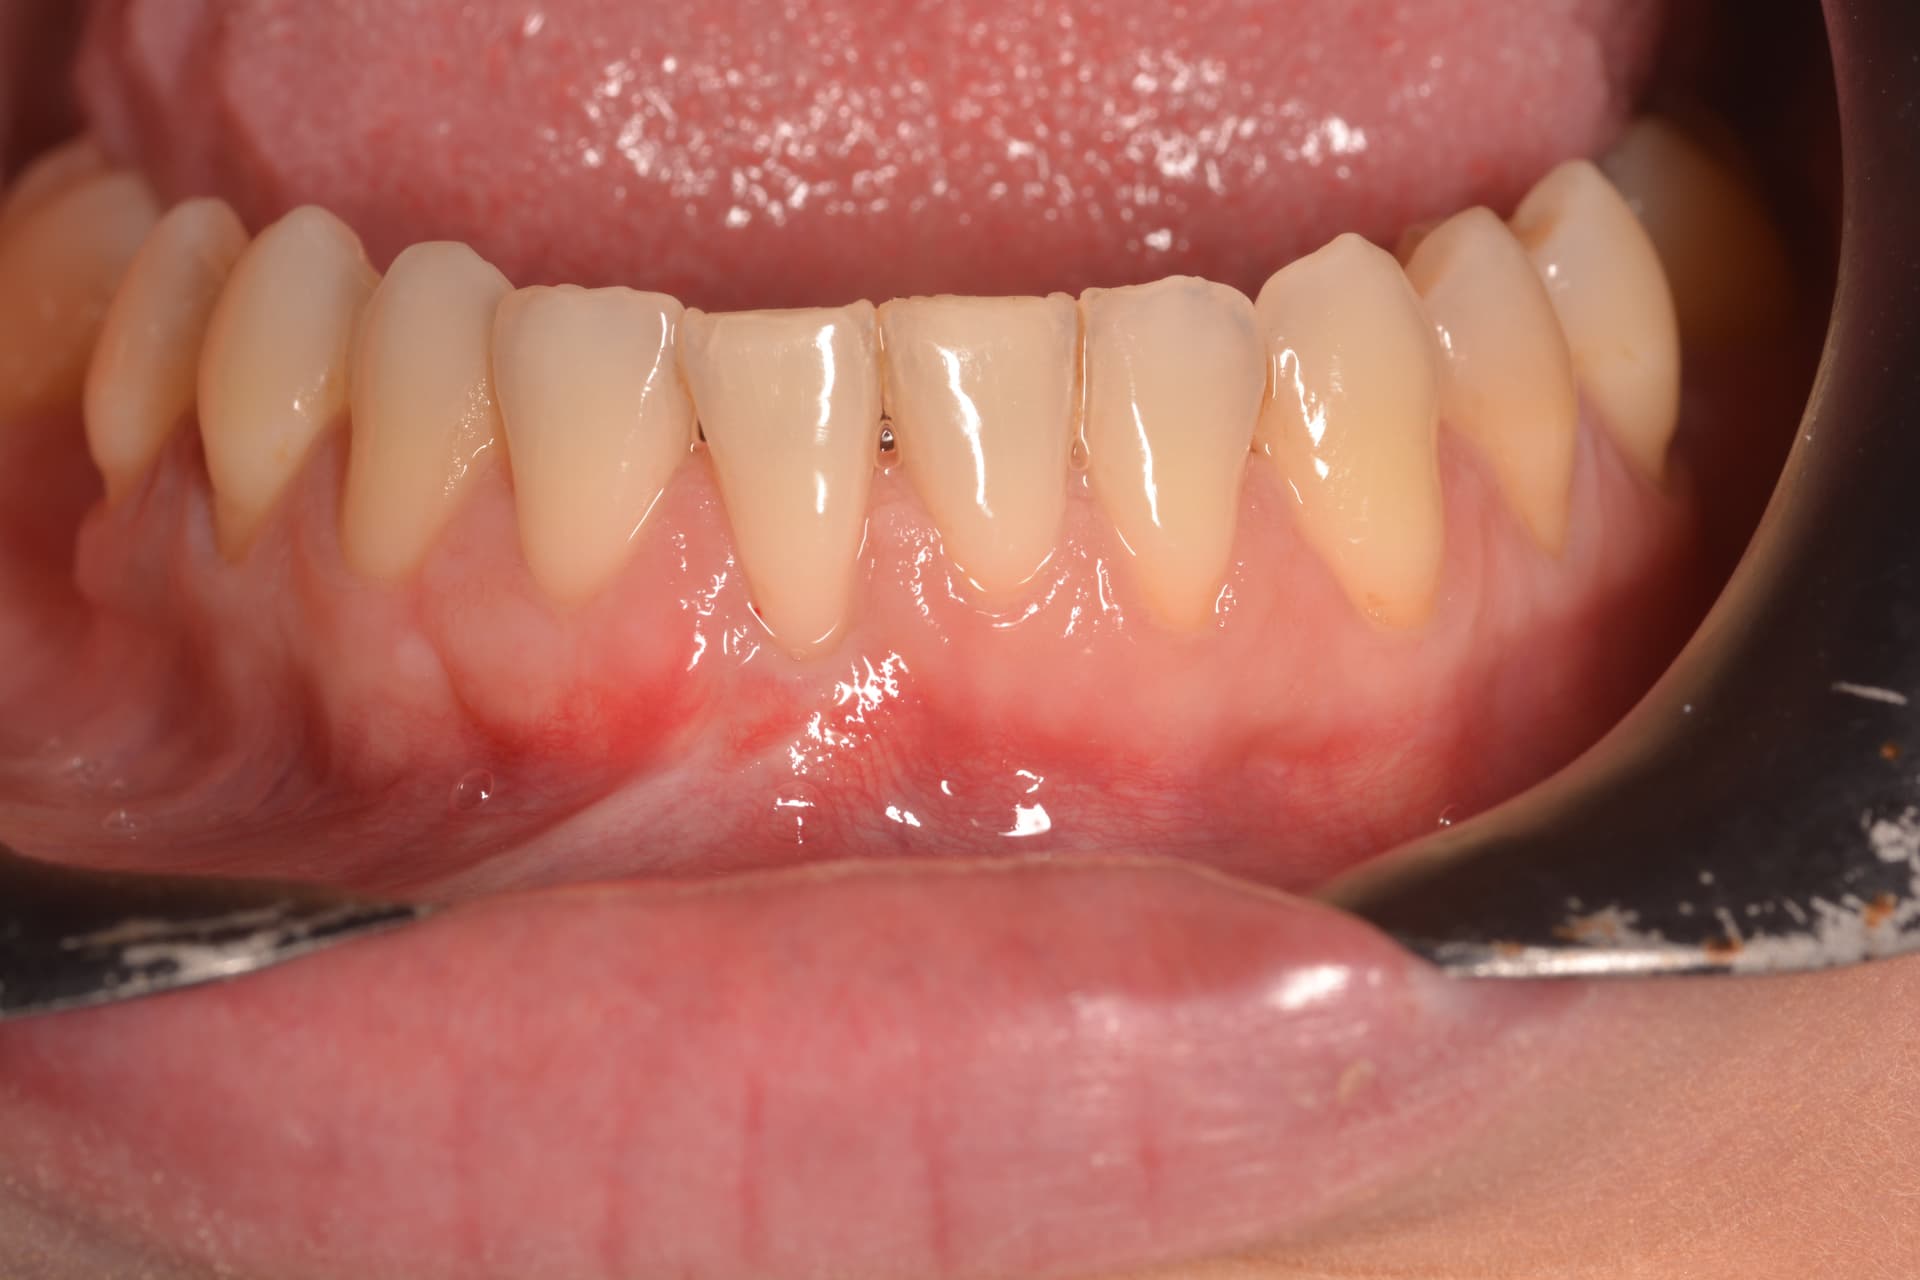

Tratamiento de recesión radicular en incisivo inferior mediante injerto de tejido conectivo